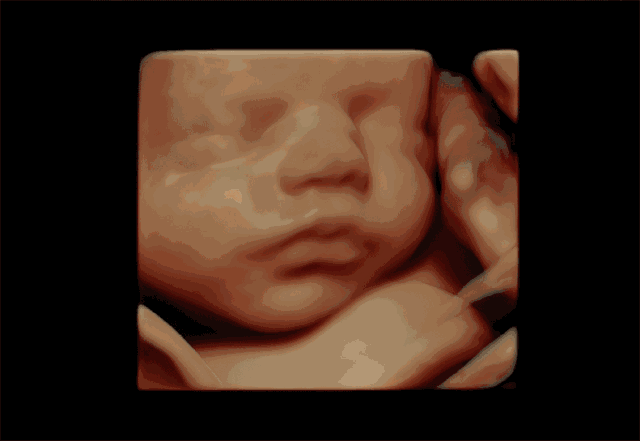

孕婦彩超是一種超聲檢查。除了一般的彩色超聲波功能外,還可以執(zhí)行胎兒頭部和臉部的立體成像。它可以清楚地顯示眼睛、鼻子、嘴巴、腹等狀況,并可以幫助醫(yī)生直接診斷胎兒先天性畸形,包括表面畸形,內(nèi)臟畸形和面部和面部畸形,可以確定胎兒在子宮中的確切位置。

四維彩色多普勒超聲在功能的基礎(chǔ)上還增加了時(shí)間維度參數(shù),并且可以實(shí)時(shí)觀察胎兒動(dòng)態(tài)的運(yùn)動(dòng)圖像,能夠更加清晰的篩查胎兒在子宮內(nèi)的狀態(tài),篩查胎兒是否有異常,提供準(zhǔn)確的科學(xué)依據(jù),及早發(fā)現(xiàn)、及早作出解決方案。

彩超是能夠監(jiān)測(cè)到胎寶寶的健康情況,其中四維彩超除了是準(zhǔn)媽媽和BB的“第一次”見面,還能夠看到ta在肚子里或活潑或文靜的可愛模樣,從而進(jìn)行重要的排畸檢查,所以也叫胎兒畸形篩查,是孕期特別重要的一次超聲檢查。

飛利浦EPIQ7高端四維彩超擁有高品質(zhì)自動(dòng)成像分析技術(shù),它可以全方位,多角度地觀察宮內(nèi)胎兒的生長(zhǎng)發(fā)育情況,為早期診斷胎兒先天性畸形,如唇裂、脊柱裂、顱腦發(fā)育異常、骨骼發(fā)育異常、心血管畸形等提供準(zhǔn)確的科學(xué)依據(jù)。